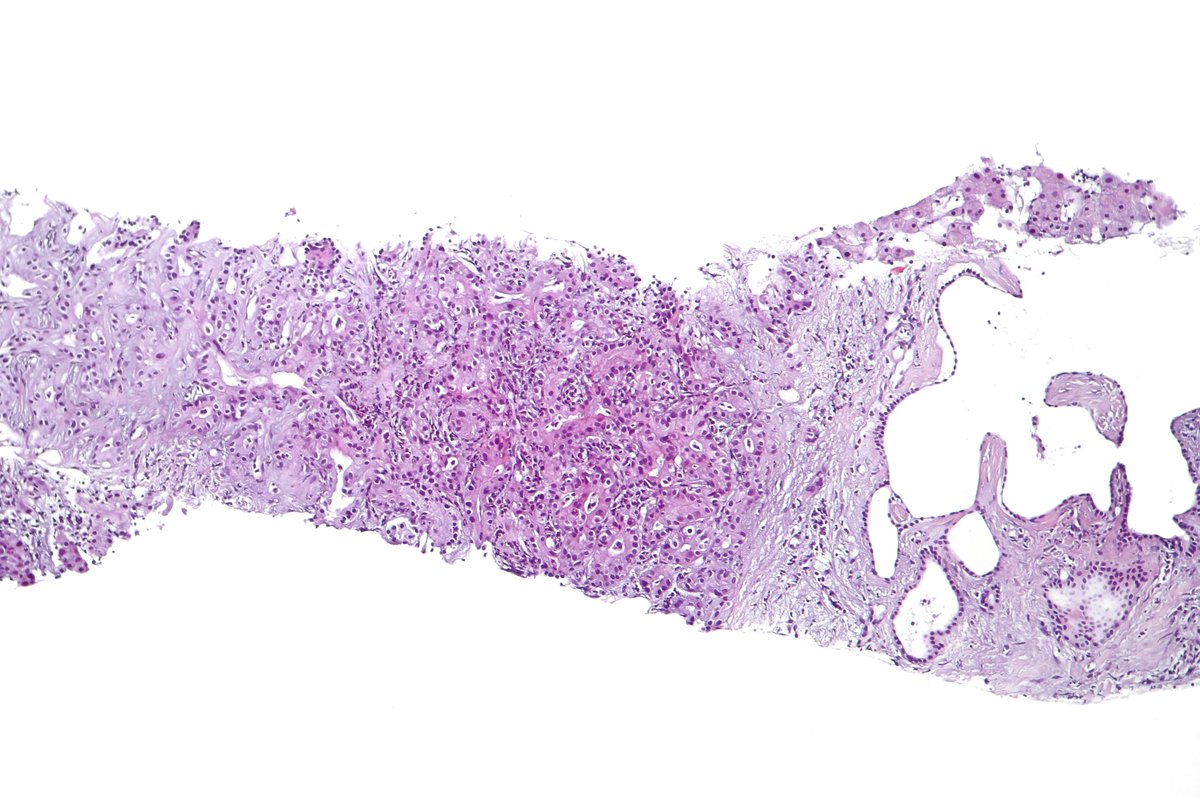

Type B2 Thymoma showing prominent large epithelial cells admixed with numerous lymphocytes. #pathology #PulmPath

@Rus13Co Dear Dr:

Can we use this picture as well for type B2 thymoma? It is really nice. Thank you very much.